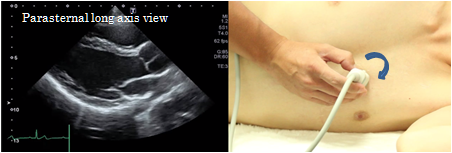

Scanning methods from long axis to short axis and to all short axis images

Rotate the probe from the left ventricular longitudinal view exactly 90 degrees clockwise to visualize the mitral orifice level. From here, tilt the probe superiorly so that the ultrasound beam is directed upward to visualize the Aortic valve level. By tilting the probe inferiorly toward the LV apex, the chordae level, papillary muscle level, and the apex level will be visualized.If visualization is difficult, move the probe in the direction of the apex and confirm the view until the left ventricular cavity becomes invisible on the scanned image. This view provides the basis for observation of the aortic valve and the mitral valve as well as evaluation of the wall thickness and wall motion abnormalities. It is important to take care not to cause oblique cutting of the image.